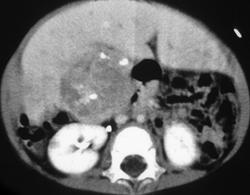

Hepatoblastoma